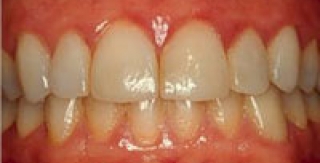

1. Bệnh nha chu có điều trị được không? Về mặt điều trị, phải lưu ý những dấu chứng lâm sàng và xem đây là các mục tiêu của điều trị nha chu.

Nha chu là bệnh của các mô quanh răng. Nếu không được điều trị, bệnh tiến triển đưa đến mất răng. Bệnh nha chu tiến triển chậm, không có các dấu hiệu gì đặc biệt, không đau, hoặc ít đau nên nhiều người thường bỏ qua. Tuy nhiên, hậu quả do bệnh nha chu gây ra lại đặc biệt nghiêm trọng, nếu được chẩn đoán và điều trị sớm có thể giảm nhẹ nguy cơ mất răng. Nguyên nhân...